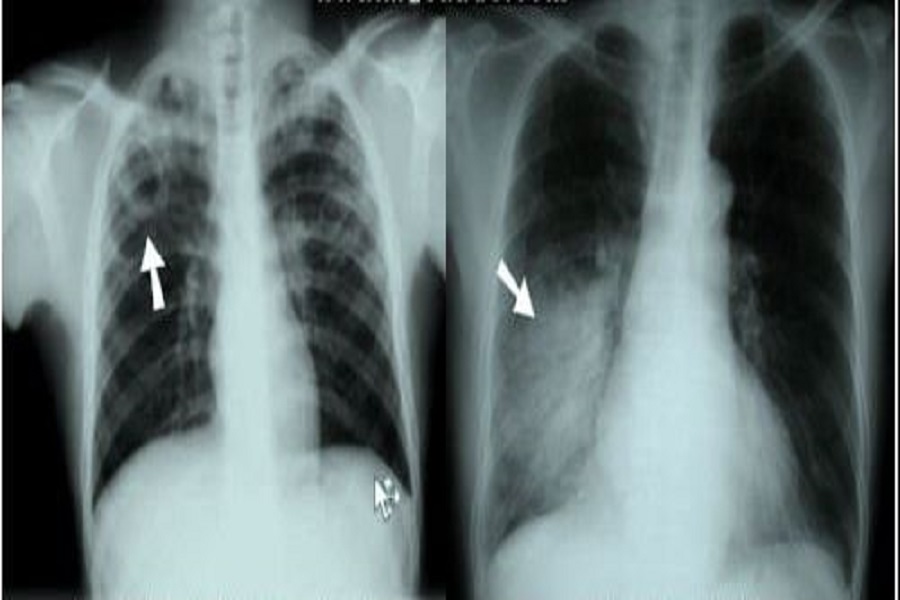

Pneumonia është ënjtja e indit në njërën ose të dyja mushkëritë e shkaktuar nga një infeksion bakterial ose viruse duke përfshirë koronavirusin.

Pneumonia është ënjtja e indeve në një ose të dy mushkëritë.